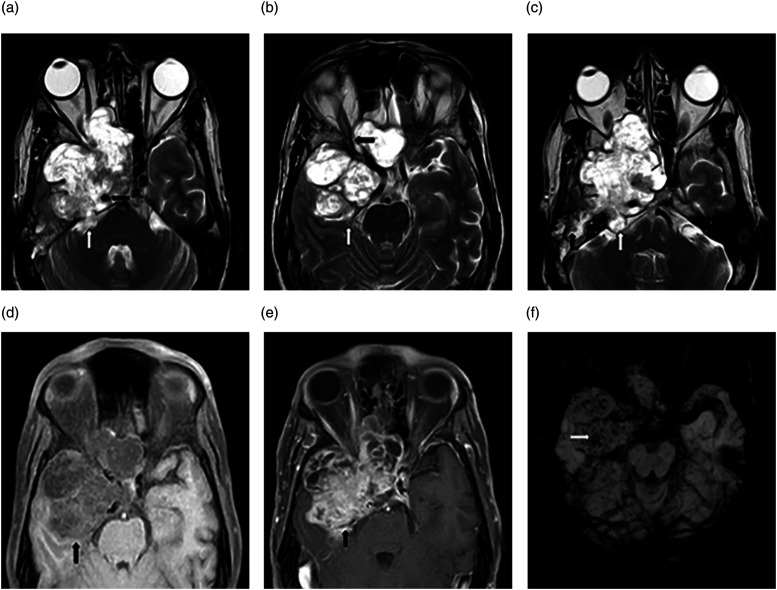

神经节血管瘤是一种罕见的肿瘤,由腹膜后和纵隔后交感神经引起。颅内三叉神经节瘤更为罕见,迄今仅有七例报道。我们报告了一例 65 岁男性的病例,他患有右侧搏动性头痛,右眼失明。磁共振成像显示,中颅窝有一个界限不清的肿块病变,少数区域的表观弥散系数降低,并有多处微出血。通过翼下和颞下入路进行右侧中开颅手术,对肿瘤进行了碎块剥离。检测到的组织学特征与三叉神经节瘤(成熟型)相符。

Ganglioneuromas are rare tumors arising from retroperitoneal and posterior mediastinal sympathetic nerves. Intracranial trigeminal nerve ganglioneuromas are even more rare, with only seven cases reported to date. We present a case of a 65-year-old male with a right-sided throbbing headache type and blindness in his right eye. Magnetic resonance imaging revealed an ill-defined mass lesion in the middle-cranial fossa, with a few areas having a reduced apparent diffusion coefficient and multiple microhemorrhages. Piecemeal debulking of the tumor was achieved by performing a right-middle craniotomy via the pterionic and sub-temporal approach. The detected histological features matched those of a ganglioneuroma (maturing type) of the trigeminal nerve.